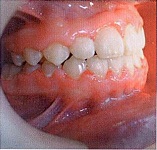

Внешний осмотр: лицо симметричное, профиль прямой. Отек верхней губы (Рис. 1).

Рис. 1

Осмотр полости рта (Рис. 2):

Рис. 2